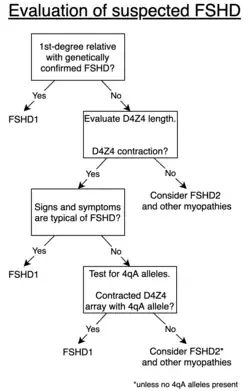

Diagnosis

FSHD can be presumptively diagnosed in many cases based on signs, symptoms, and/or non-genetic medical tests, especially if a first-degree relative has genetically confirmed FSHD.[10] Genetic testing can provide definitive diagnosis.[4] In the absence of an established family history of FSHD, diagnosis can be difficult due to the variability in how FSHD manifests.[86]

Genetic testing

Genetic testing is the gold standard for FSHD diagnosis, as it is the most sensitive and specific test available.[2] Commonly, FSHD1 is tested for first.[2] A shortened D4Z4 array length (EcoRI length of 10 kb to 38 kb) with an adjacent 4qA allele supports FSHD1.[2] If FSHD1 is not present, commonly FSHD2 is tested for next by assessing methylation at 4q35.[2] Low methylation (less than 20%) in the context of a 4qA allele is sufficient for diagnosis.[2] The specific mutation, usually one of the various SMCHD1 mutations, can be identified with next-generation sequencing (NGS).[87]